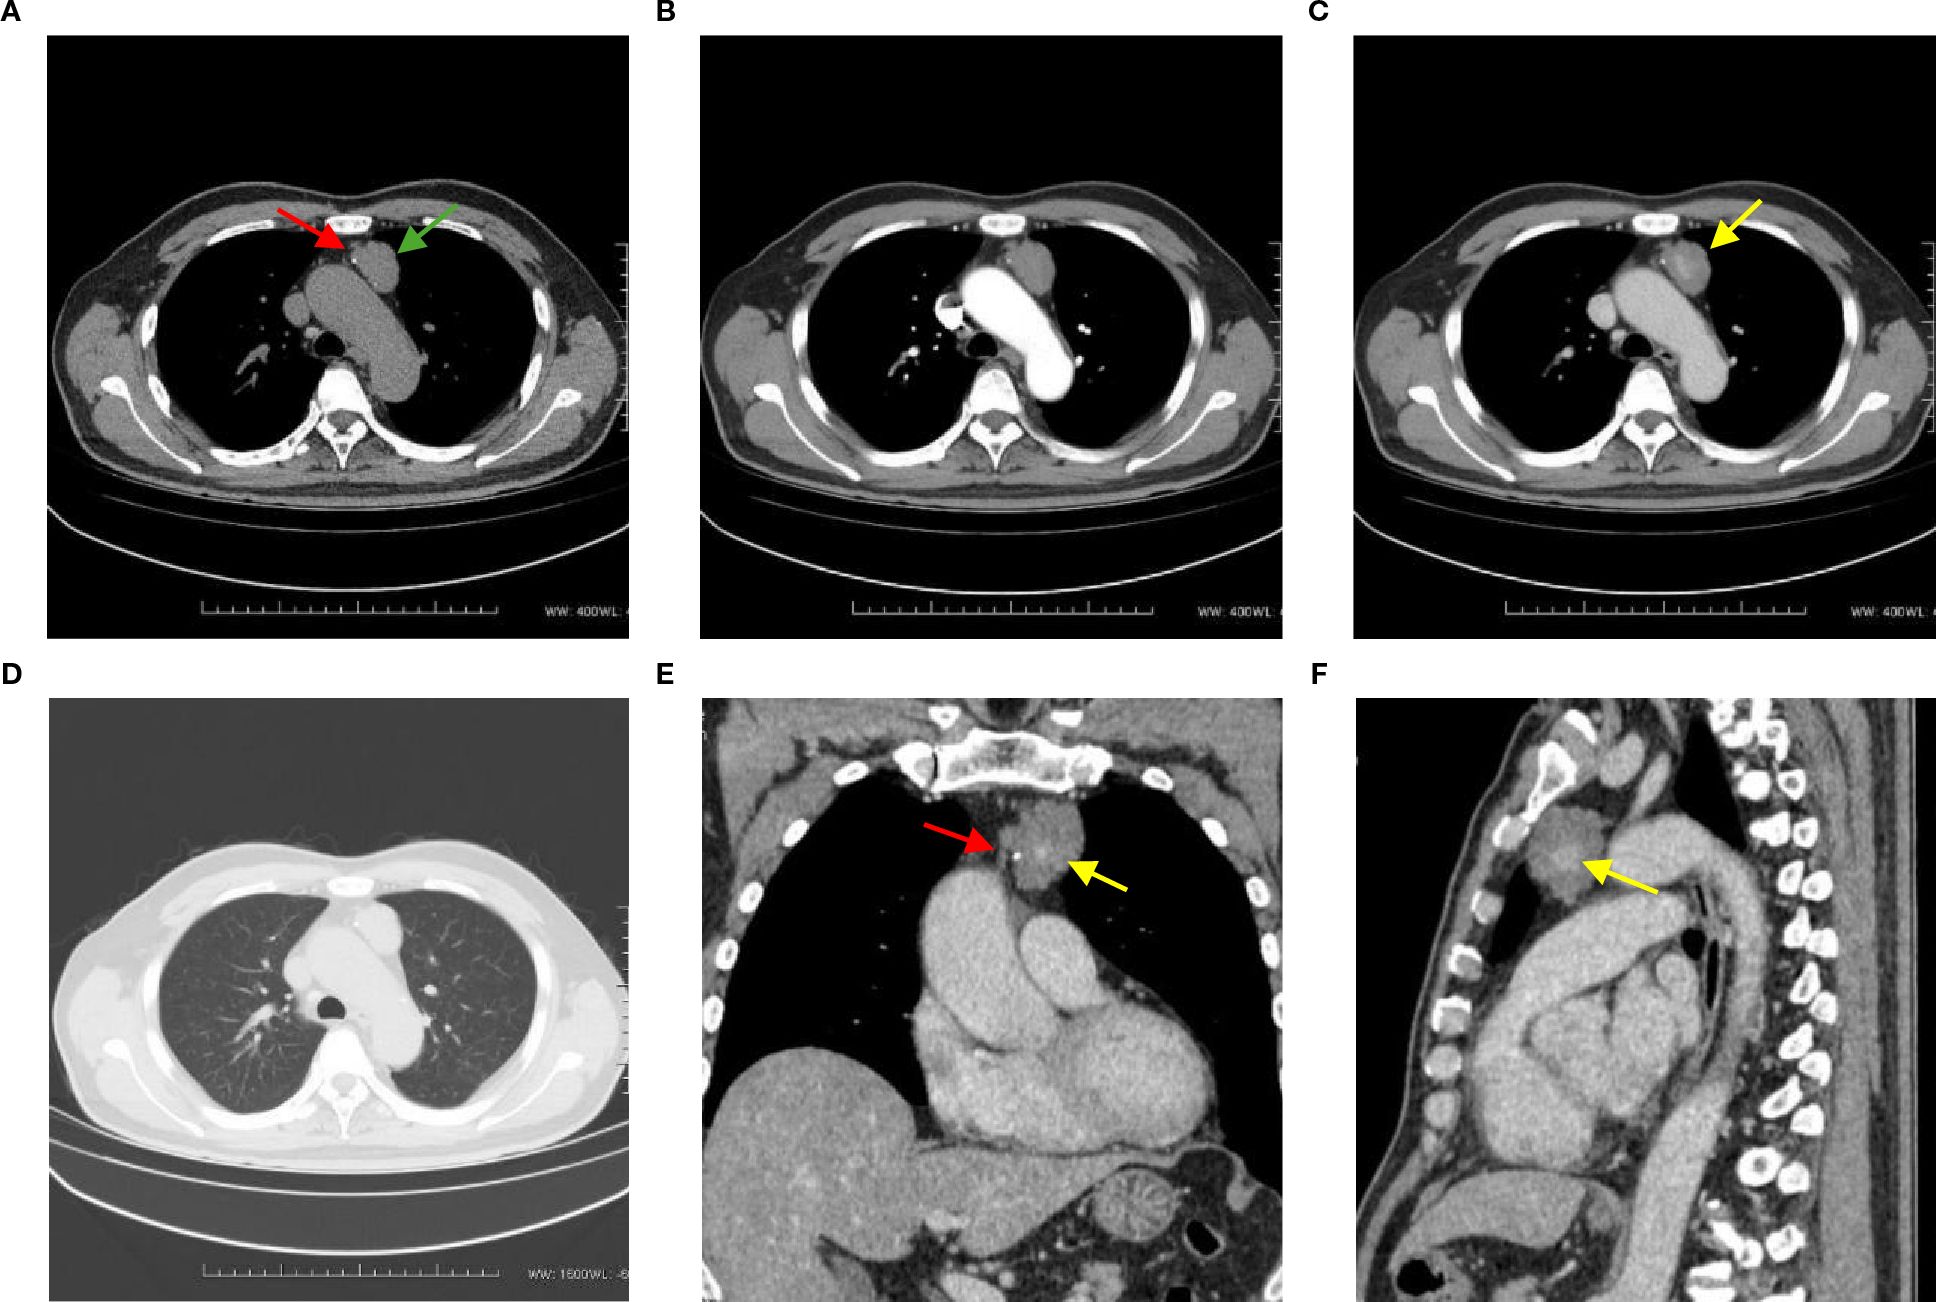

A 72-year-old man presented with an anterior mediastinal mass eight years ago and was recently admitted to the hospital due to an increase in the size of the mass. The patient did not exhibit any abnormal clinical manifestations, family history, medical history, physical examination findings, or abnormal laboratory test results. He had no clinical features suggestive of tuberous sclerosis complex (TSC). Specifically, he did not have central nervous, hydrocephalus, mental retardation. He did not have dermatologic manifestations. He did not have a family member who was diagnosed with TSC. A plain chest computed tomography (CT) scan revealed an irregular hypodense mass measuring 3.5 cm × 3.0 cm × 1.9 cm on the left side of the anterior superior mediastinum. The mass had a CT value of 45.3 HU and displayed clear borders. Punctate calcification was observed at the edge of the lesion (Figure 1A). In the arterial phase, the mass did not exhibit significant enhancement, with a CT value of 46.1 HU (Figure 1B). However, during the venous phase, the mass showed striated enhancement in the central area, while the marginal area displayed no abnormalities. The CT values in the venous phase were 94.6 HU in the central area and 46.3 HU in the marginal area (Figure 1C). No enlarged lymph nodes were observed in the hilum, and the mass did not exert pressure on surrounding tissues or blood vessels. There was also no evidence of infiltration, and the lung window displayed clear lung texture without cystic changes (Figure 1D).

Figure 1

(A) This axial CT image shows an irregular hypodense mass in the left side of the anterior superior mediastinum, with clear boundaries (green arrow). Punctate calcification is observed at the edge of the lesion (red arrow). (B) This CT image in the arterial phase demonstrates that the mass does not exhibit significant enhancement, with a CT value of 46.1 HU. (C) In the venous phase CT image, striated enhancement is observed in the central area of the mass, while no abnormalities are seen in the marginal area (yellow arrow). The CT values are 94.6 HU and 46.3 HU, respectively. (D) The lung window image shows a clear texture in both lungs, with no evidence of cystic changes. (E, F) Coronal and sagittal reformations further illustrate the striated enhancement in the central area of the mass (yellow arrow), as well as the presence of punctate calcification at the edge of the lesion (red arrow). The mass does not exert any obvious pressure on the surrounding tissues and blood vessels, and there is no evidence of infiltration.

In our present case, the CT scan showed an irregular hypodense mass with clear borders and punctate calcification at the edge. This is consistent with previous findings reported in the literature (19). The mass did not demonstrate significant enhancement in the arterial phase, while in the venous phase, it showed striated enhancement in the central area and no abnormalities in the marginal area. The central enhancement in the venous phase may be associated with clusters of thickened tubular structures in the center of the mass. When LAM lesions contain solid components, the venous phase of CT may demonstrate mild to moderate enhancement. Pathologically, this is related to the presence of proliferating smooth muscle cells, fibrous tissue, and possible neovascularization within the solid components. The neovascularization may allow the solid components to absorb contrast agents during the CT venous phase, thereby exhibiting enhancement. In this case, the mass did not exert any obvious pressure on the surrounding tissues or blood vessels and did not manifest infiltration. The higher CT value observed on the plain chest CT in this case may be attributed to the high protein content within the lesion.